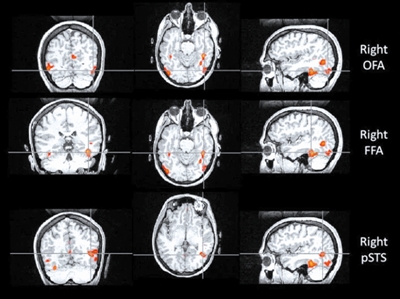

与认脸有关的三个核心脑区,自上而下依次为:OFA(枕叶面孔区)、FFA(梭状回面孔区),以及 STS(上颞沟)

比如,位于枕叶的枕叶面孔区(Occipital Face Area, OFA),就像识脸网络的“先锋部队”。它专门处理眼睛、鼻子和嘴巴等五官“零部件”。当一张脸出现在我们眼前时,OFA 只需 约 100 毫秒就能被激活,迅速对局部特征进行拆解,并将信息传递给 FFA 和上颞沟(Superior Temporal Sulcus, STS)。所以如果 OFA 出现问题,识别人脸就会变得很困难。

如果说 OFA 的作用是拆解五官,那么 STS 则更像是一个“动态解码器”。它对静态的面孔特征兴趣不大,却对动态特征极为敏感,尤其擅长捕捉 一颦一笑、眼神转动、嘴唇开合等细微变化。

正因为有 STS 的参与,我们不仅能认出“这是谁”,还能理解“他在表达什么情绪”“注意力投向哪里”,甚至在一定程度上推测对方的意图。STS 的参与也解释了为什么比起静态照片,在现实生活或视频中,我们更容易认出熟人。